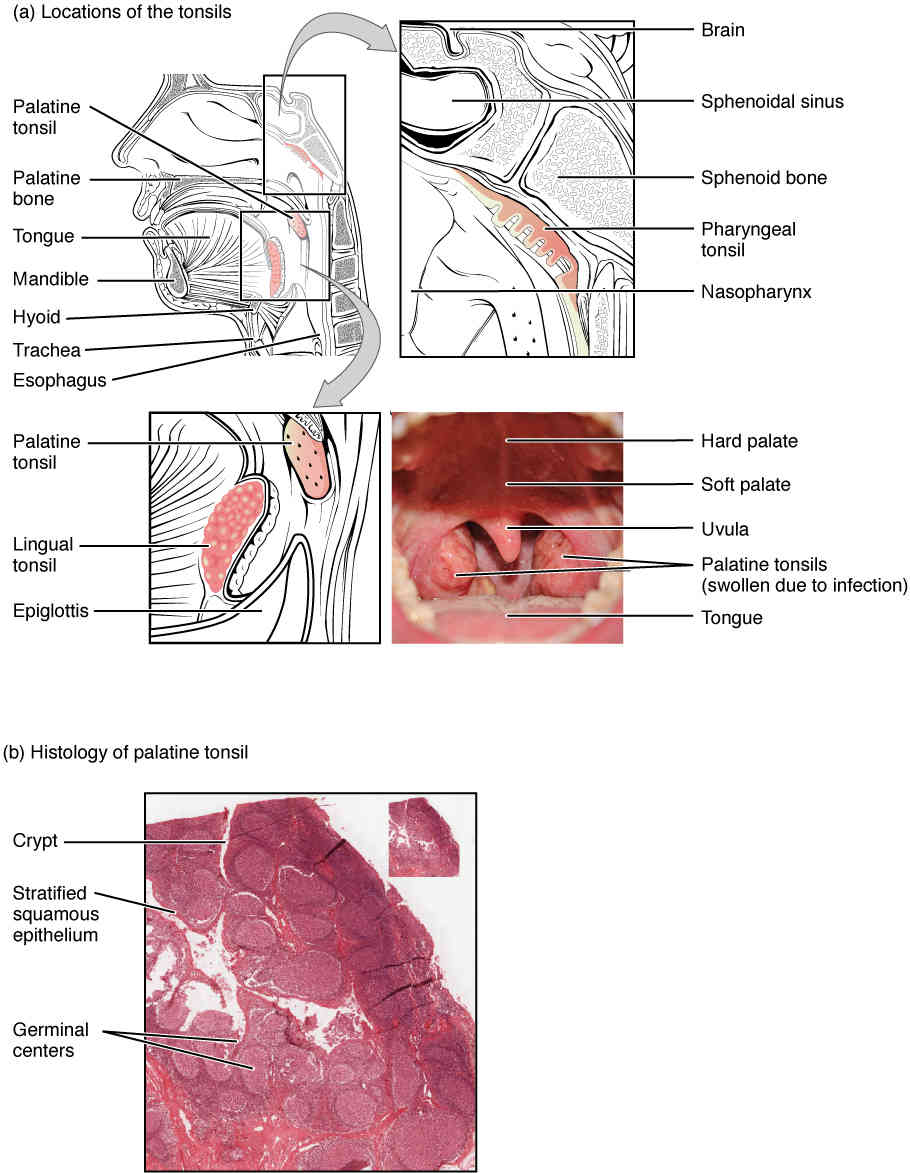

This page is under construction. For now, it is just a resource of the images found in the OpenStax Anatomy and Physiology Handbook. It wil slowly change into a revision tool. Each slide has a number. Use this to refer to the slide. When completed, it will have an unlabelled section, with labelled slides in parallel. On the unlabelled slides, write your answer and use the labelled slide to assess yourself. Keep track by also noting the number on each slide. Improvement at each attempt is important, more so than full marks on a first attempt.